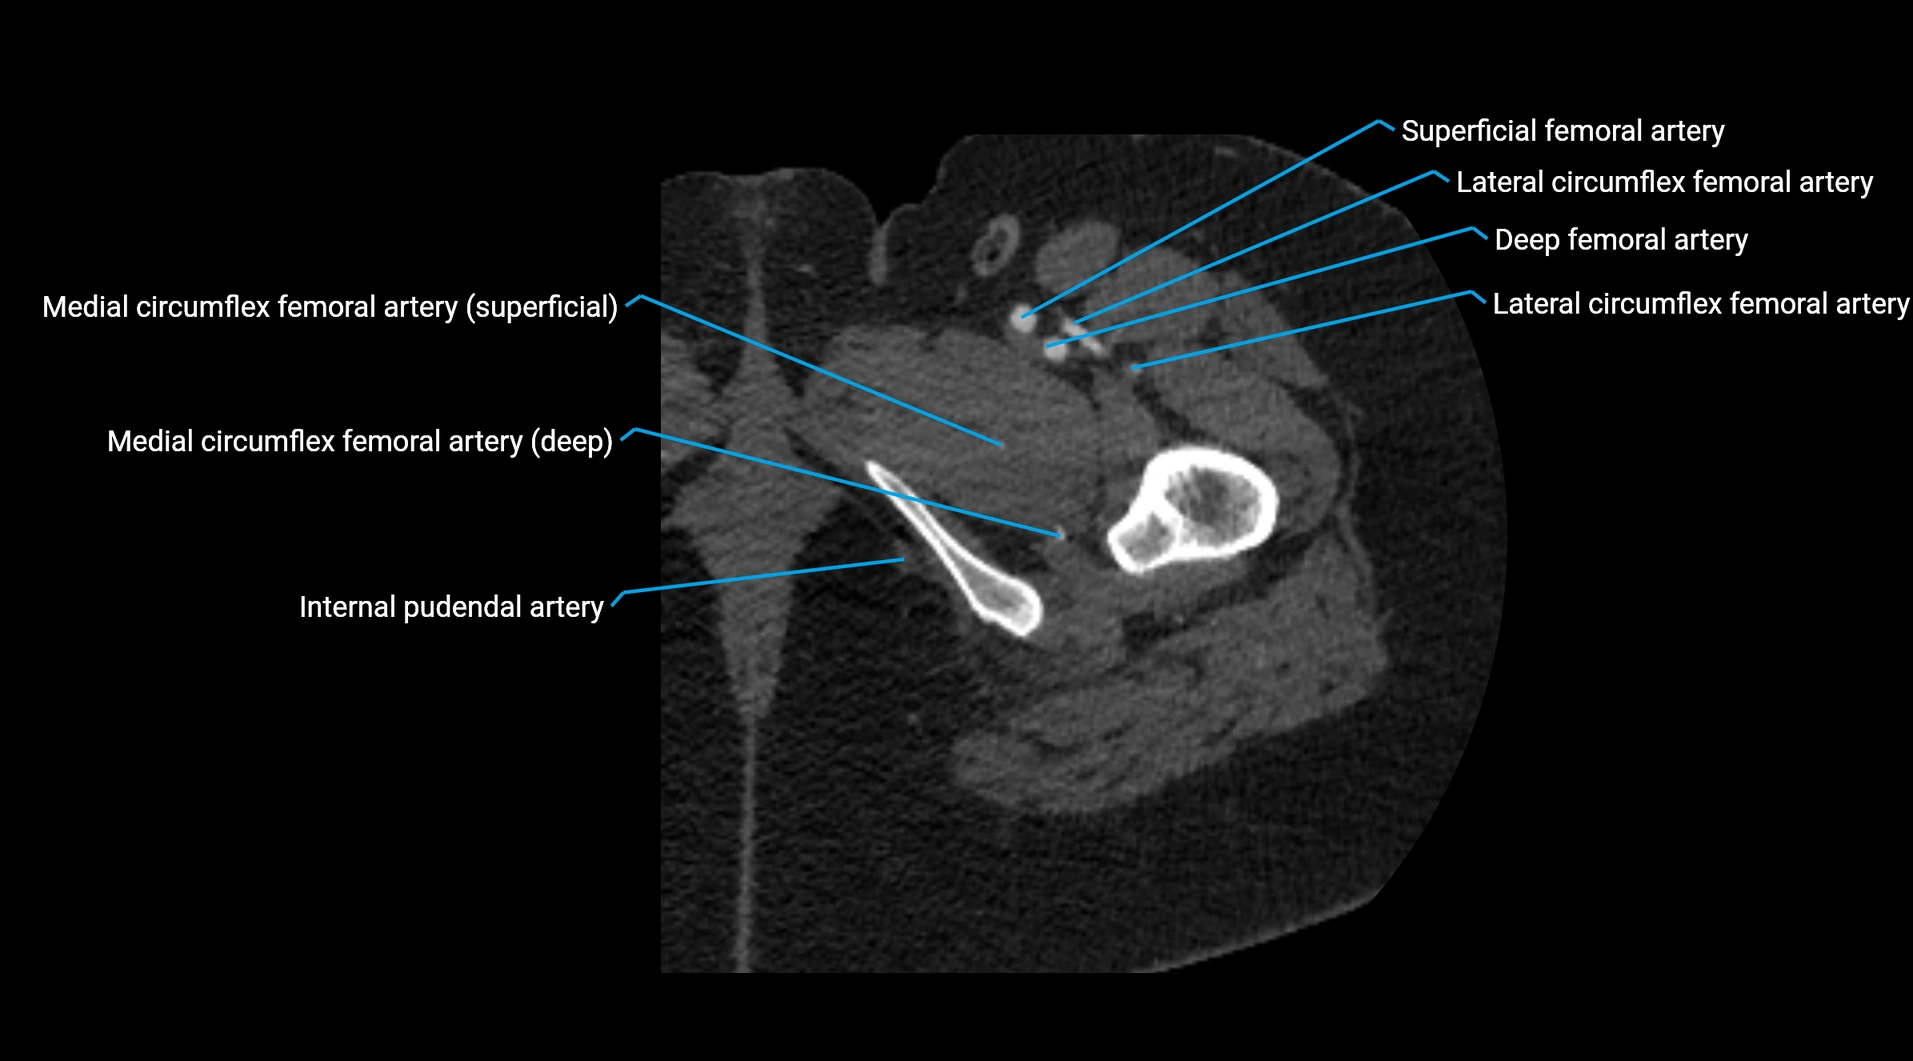

CT images

image